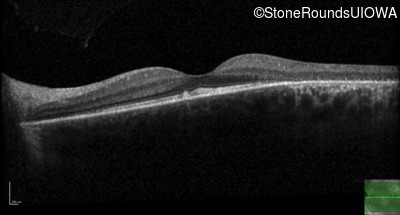

Optical Coherence Tomography - Right - 20/20 -1

Exemplar / OCT Stack

OCT Stack